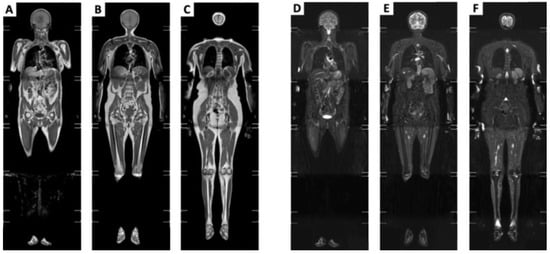

2. MRI Whole-Body Protocols

3.2. Biomarker for the Evaluation of the Treatment and Follow-Up (Quantitative Assessment)

- Filli, L.; Maurer, B.; Manoliu, A.; Andreisek, G.; Guggenberger, R. Whole-body MRI in adult inflammatory myopathies: Do we need imaging of the trunk? Eur. Radiol. 2015, 25, 3499–3507. [Google Scholar] [CrossRef]

- Baudin, P.-Y.; Marty, B.; Robert, B.; Shukelovitch, A.; Carlier, R.Y.; Azzabou, N.; Carlier, P.G. Qualitative and quantitative evaluation of skeletal muscle fatty degenerative changes using whole-body Dixon nuclear magnetic resonance imaging for an important reduction of the acquisition time. Neuromuscul. Disord. 2015, 25, 758–763. [Google Scholar] [CrossRef]